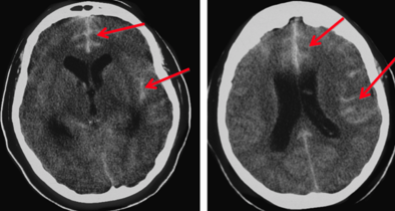

A patient presents with worsening headache, nausea and vomiting and drowsiness. CT brain reveals dilated ventricles due to an obstruction in the ventricular system

Hydrocephalus